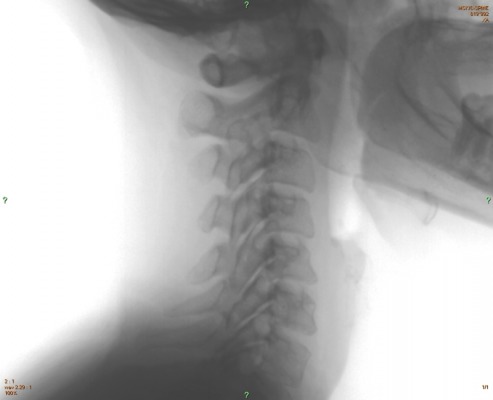

Here are magnified and negative views of the lateral cervical which may make it easier to see some of the lesions.